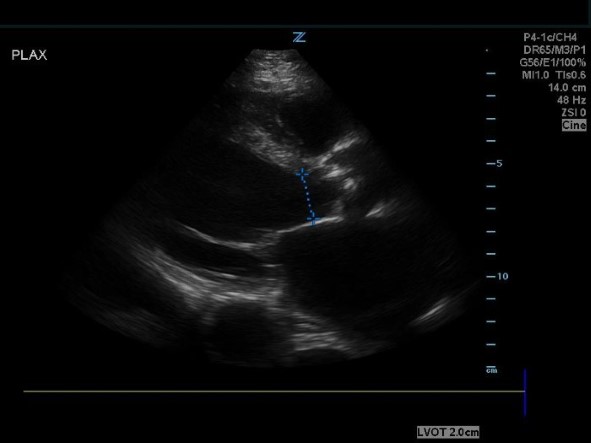

- Obtain a PLAX and measure the LVOT cross sectional area (by measuring LVOT diameter).

Figure 4. PSAX view measuring the LVOT cross sectional area.